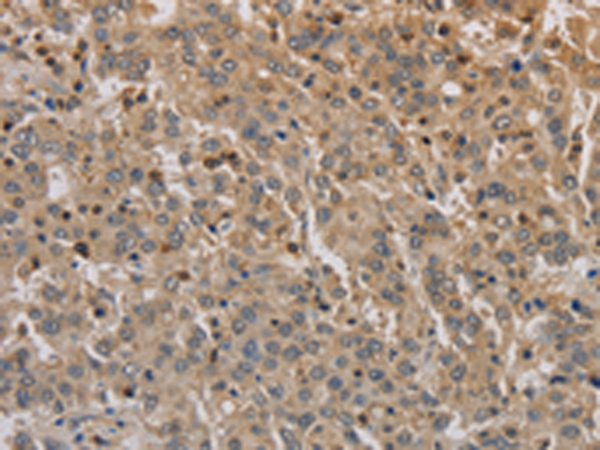

分类: 科研抗体货号: P10649别名: BETA3AR应用: IHC反应种属: Human